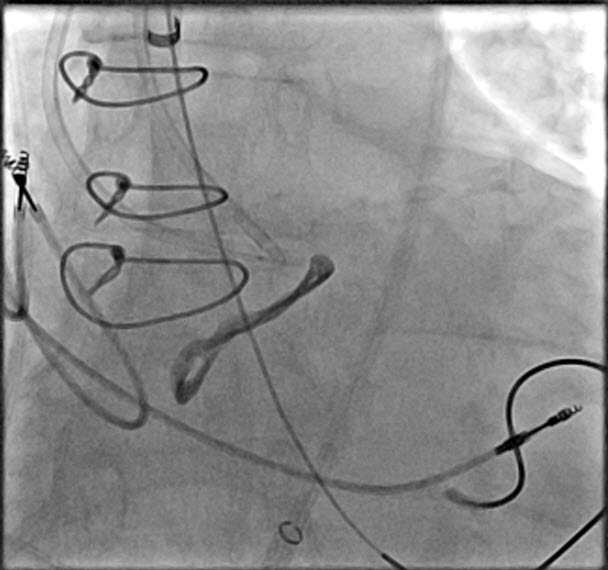

LV pacing TAVR.

#TAVR#LVpacing. Valve in valve. Patient has already a permanent pacer. LV pacing can be done as a routine in those scenarios.pic.twitter.com/qrBFSjFfMn -